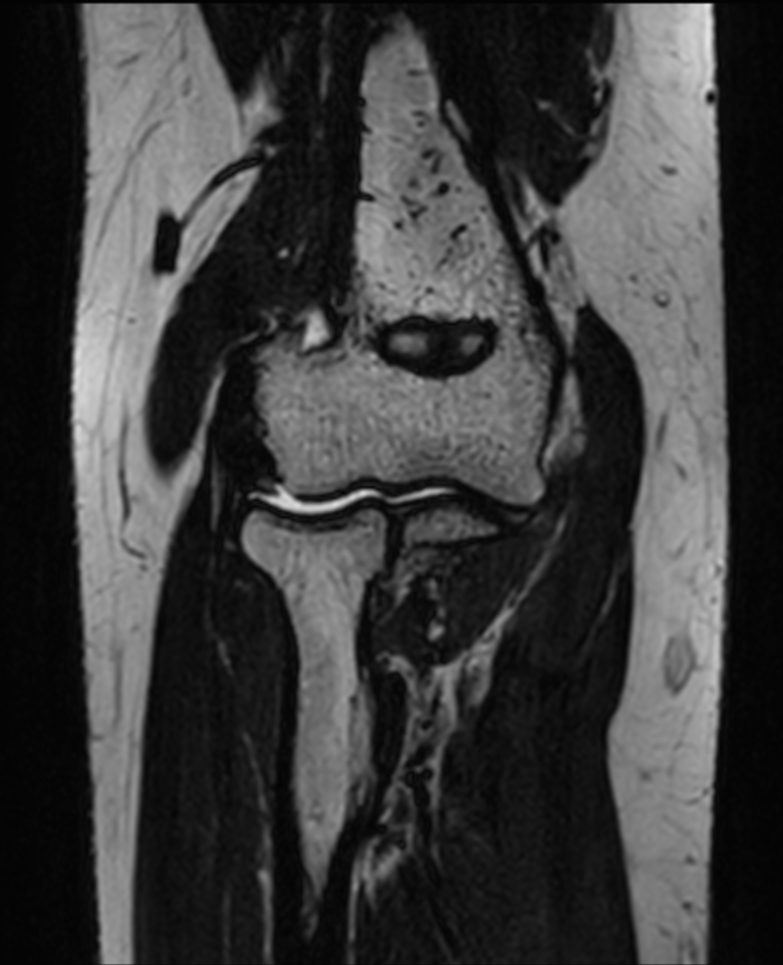

Large FOV imaging with the dS 16ch Small Extremity coil

Used Solution

• System

• Coil

• Clinical Application